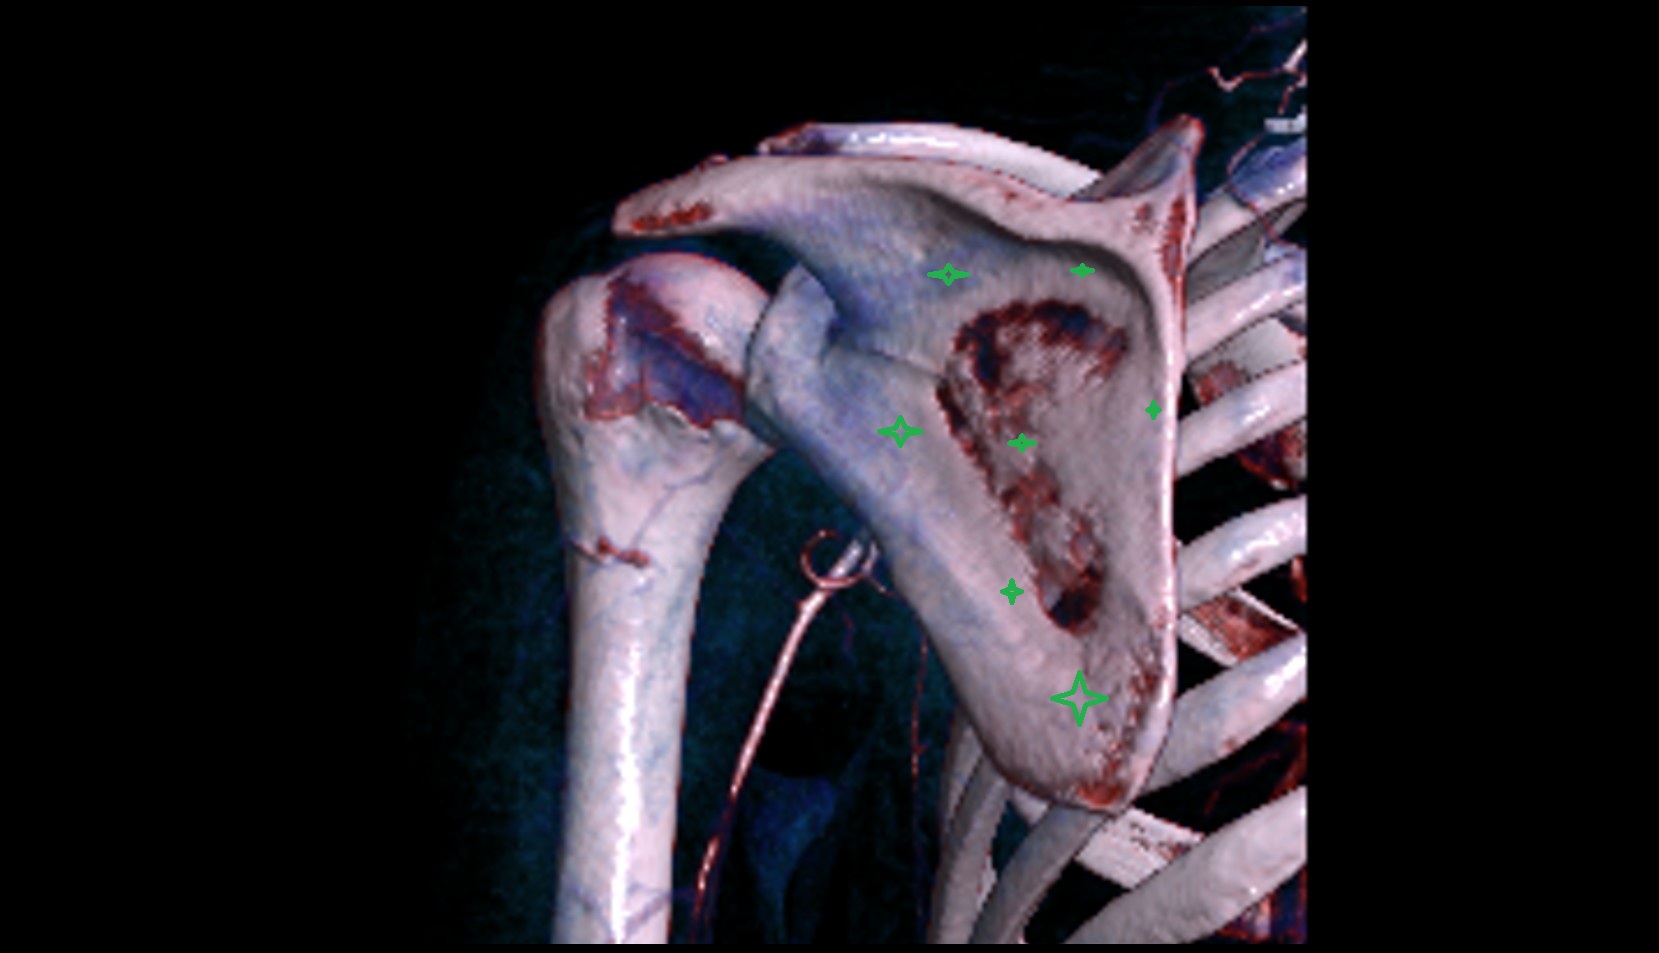

- Shoulder joint (glenohumeral joint)

- Acromioclavicular joint